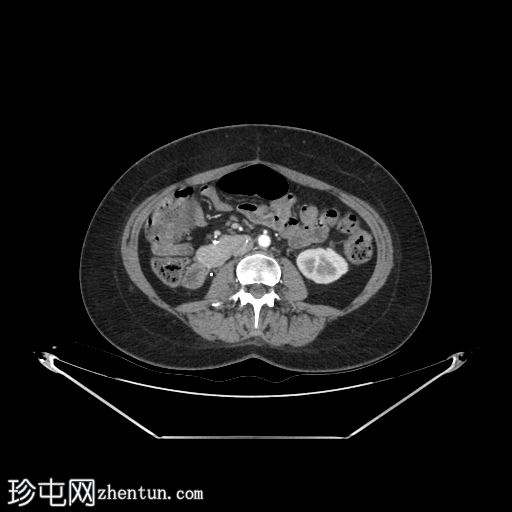

轴位增强扫描

门静脉期

自体肾脏和胰腺(胰头、胰体和胰尾)明显萎缩。

移植的胰腺位于右侧腹膜后间隙,大小和形态(轴位、冠状位和矢状位)均正常,可见相关手术缝合线。供体十二指肠段与自体十二指肠吻合。可见胰腺移植物与右髂血管的动脉吻合,胰腺实质强化均匀,提示移植物灌注良好。

左髂窝肾移植(轴位、冠状位),显示移植肾与同侧髂总血管的动脉和静脉吻合。移植肾形态完整,实质均匀强化。

本例中,影像学检查显示原位肾脏和胰腺明显萎缩,符合长期糖尿病合并慢性肾脏病的表现。肾移植位于左髂窝,与同侧髂血管的动脉和静脉吻合通畅,肾实质均匀强化,这些影像学表现均符合功能性肾移植的影像学特征。移植胰腺位于右侧腹膜后,形态和位置均符合原位胰腺,供体十二指肠袢与原位十二指肠吻合良好。